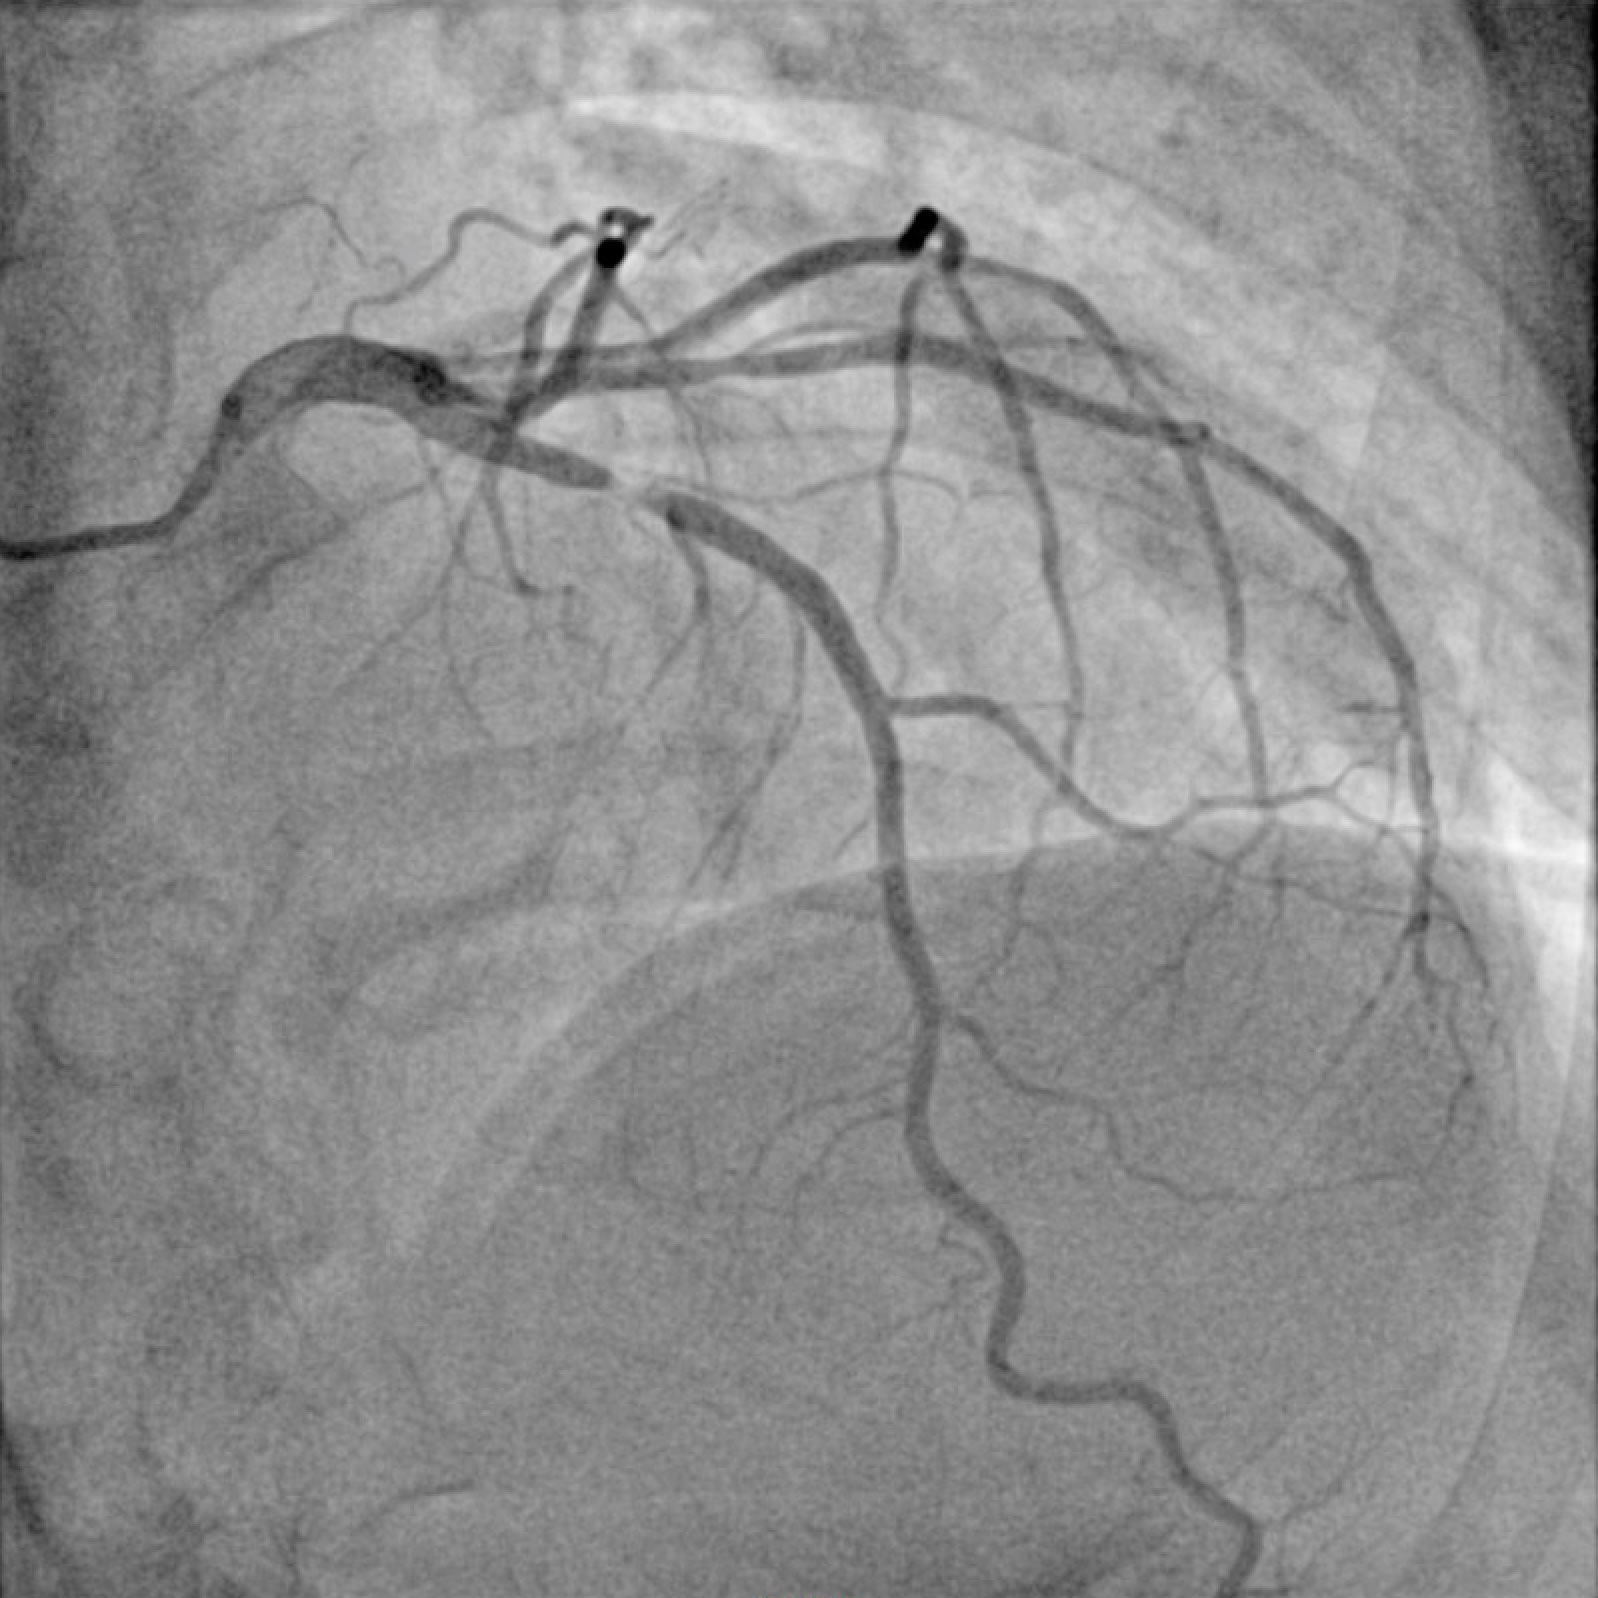

Coronary angiography was performed via right radial access. Angiography demonstrated a right dominant system with severe (95%) proximal LAD stenosis - 30 mm long Type C lesion.

- Baseline LAD Angiogram